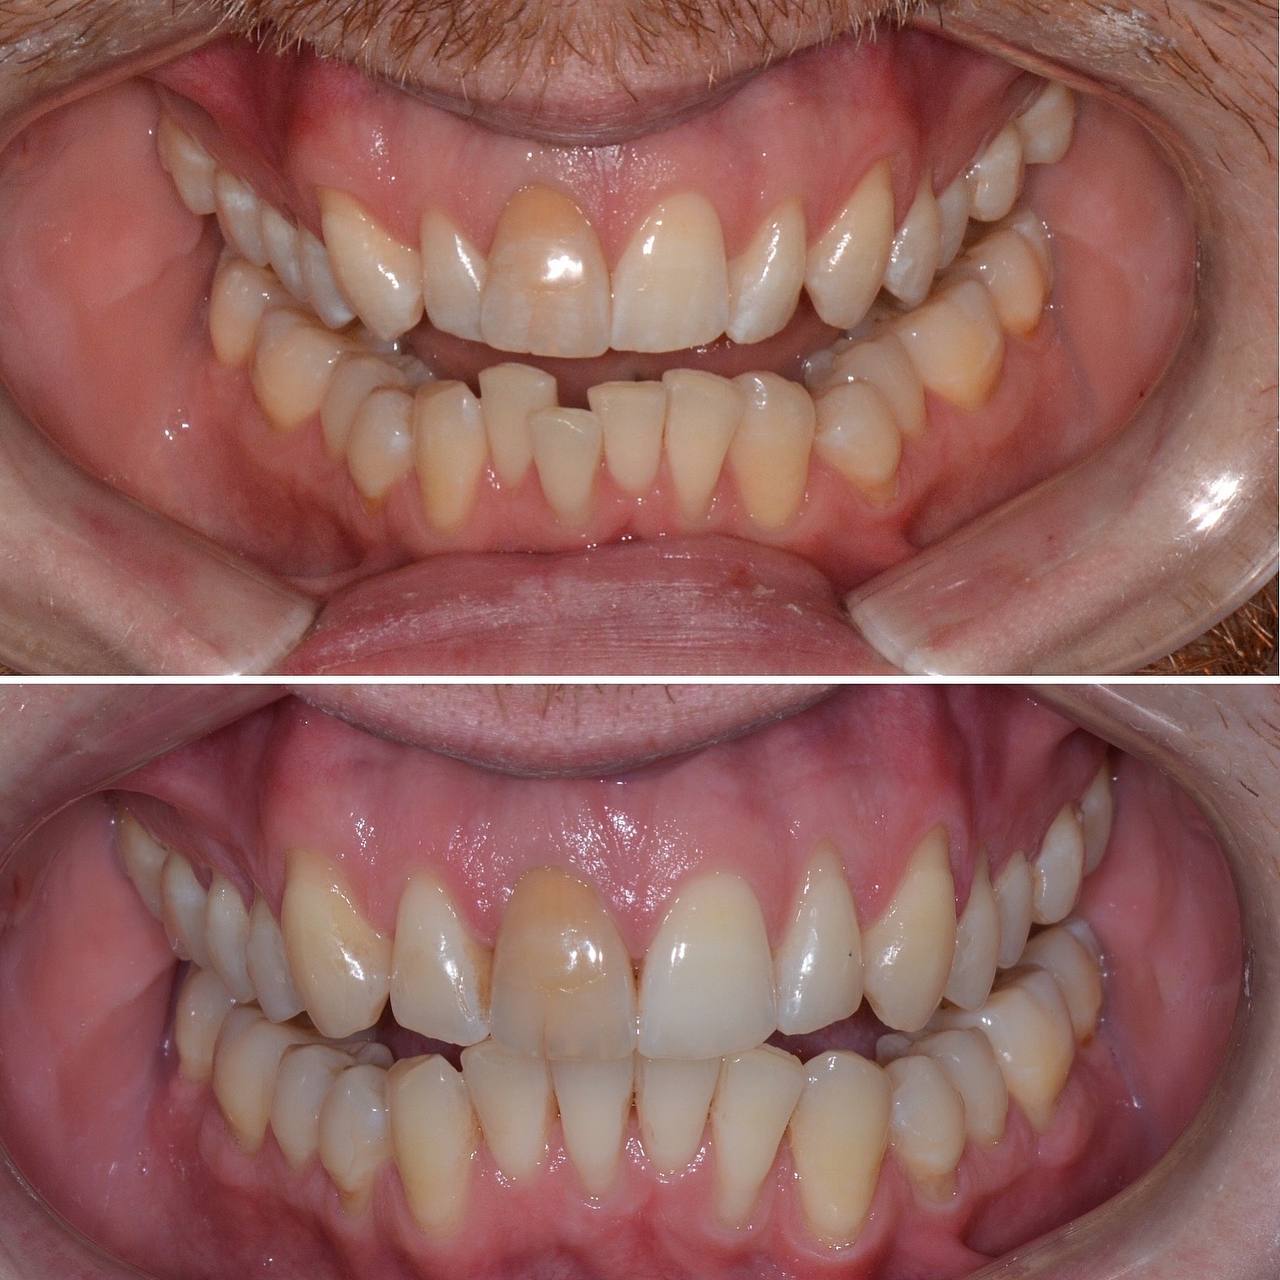

К нам с стоматологию обратился пациент с желанием сделать улыбку красивее. Лечением занимался стоматолог-ортодонт. Прикус и кривизну зубов исправляли при помощи элайнеров. Лечение заняло 12 месяцв. За это время было использовано 30 комплектов элайнеров.

Фото до и после лечения зубов элайнерами